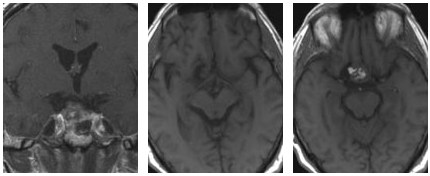

本例患者术前磁共振成像清晰显示,一个大型垂体瘤不仅向上生长压迫视交叉,更向侧方侵袭,侵犯了右侧海绵窦。这意味着,肿瘤已与上述生死攸关的血管及神经结构紧密交织。

术前MR显示患者存在一个大型垂体肿瘤(箭头所示),该肿瘤向上生长并紧密靠近垂体区域(位于鞍上和鞍旁),侵犯海绵窦。

术后复查的磁共振成像给出了明确的结果:肿瘤被完全切除,受侵犯的海绵窦得到解放,周围所有重要结构均完好无损。患者不仅解除了肿瘤占位压迫的威胁,更保全了全部的神经功能——未出现新增的复视、无视力下降、垂体各项功能维持正常。

术后MRI结果显示,该患者的肿瘤已完全切除,且使用了脂肪组织进行了封闭处理。